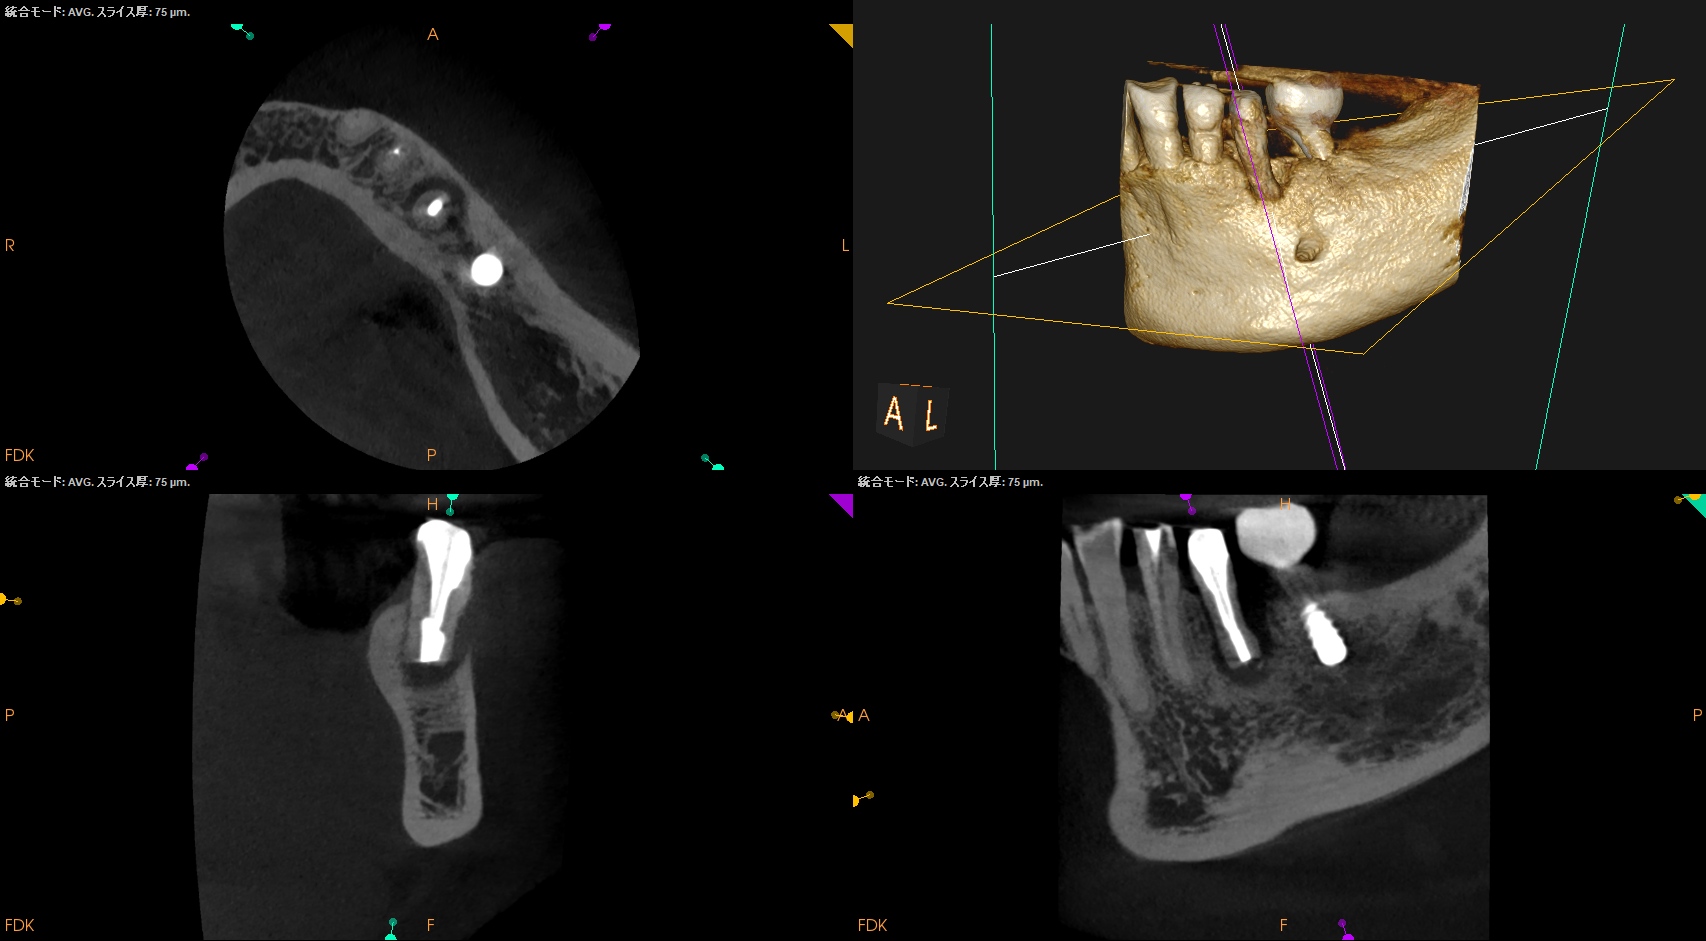

昨日の処置の後、#20 Intentional Replantationを行っていた。

頬側の皮質骨は既にない。

VRFを想像させる絵だが、

術前の歯周ポケット測定では、#20は全周、Within Normal Limit(正常の範囲内)である。

術後にPA, CBCTを撮影した。